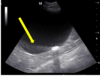

what is this?

Dilation of renal pelvis

Chunky ureters

What is going on?

Hydronephrosis/ dilated ureters